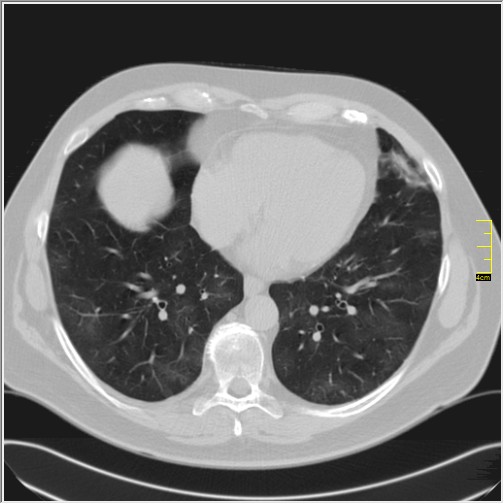

Četiri dana kasnije. Isti pacijent dolazi sa istim pulmologom. Situacija je sada sasvim drugačija. Temperatura 39.5 C. Saturacija 92. Laboratorija daleko gora. Uradim CT pluća. Ovo je izašlo.

Severity score 15/25. Pacijent je upućen na bolničko lečenje.

Ono što zbunjuje, a to se ponavlja zadnjih 10 dana, je da fibroza nastupa u progresivnoj fazi, znači na početku bolesti. Toga nije bilo do sada. Sledećih dana ću o tome.

Ovo je samo 4 dana. Od zdravlja do teške bolesti. Pacijent je 45 godina starosti, očigledno nije povećane težine, kaže za sebe da je bio sportista. U anamnezi nije naveo nikakve bitne bolesti.